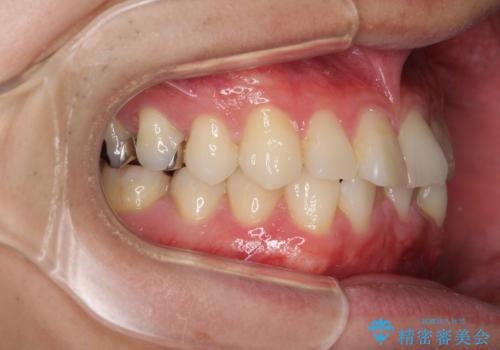

- 30代男性

- 矯正装置

- 審美装置

- 治療期間

- 1年2ヶ月

- 右下奥歯の虫歯がしみて痛いとのことで来院された患者様です。

神経近くにまで及ぶ大きな虫歯でしたが、速やかに処置を行い、痛みは即日解消されました。

虫歯が大きかったため、クラウンによる補綴治療が必要になる旨をお伝えしたところ、矯正治療にも興味があるとのことでした。

短期間で手間のかからない方法がご希望でしたので、ワイヤー装置による矯正治療を行うこととし、矯正治療後に右奥2歯をセラミッククラウンにて補綴することとしました。